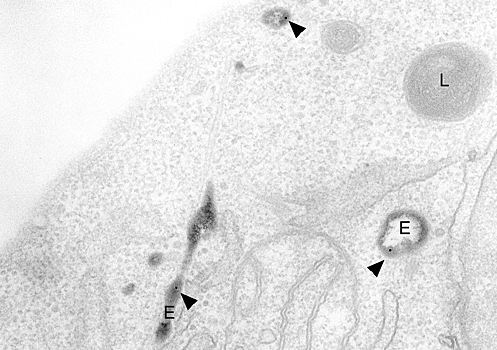

Сотрудники факультета фундаментальной медицины МГУ имени М. В. Ломоносова Алибек Абдрахманов и Владимир Гогвадзе провели исследование разнообразных форм аутофагии – процессов уничтожения клеткой собственных органелл и молекул. Также были рассмотрены механизмы их регуляции и взаимодействия друг с другом. Работа, проведенная при поддержке Российского научного фонда, опубликована в Trends in Biochemical Sciences. В рамках исследования ученые проанализировали более 120 современных литературных источников, содержащих информацию о процессах, лежащих в основе этого важного для организма феномена. Клетки нашего организма обладают уникальной способностью в критических ситуациях, например, при нехватке питательных веществ или повреждениях, – они могут запускать механизмы утилизации собственных органелл и макромолекул. Это помогает поддержать энергетические запасы и обеспечить клетку «строительным материалом». В ходе такого процесса, названного аутофагией (в переводе с греческого языка «самопоедание»), поврежденные и/или излишние компоненты утилизируются внутри самой клетки в особых клеточных отделах, или компартментах. Впервые аутофагия была охарактеризована бельгийским биохимиком, первооткрывателем лизосом (своего рода клеточных «желудков») Кристианом де Дювом, получившим Нобелевскую премию в 1974 году. Спустя много лет, в 2016 году, японскому исследователю Ёсинори Осуми была присуждена Нобелевская премия в области физиологии или медицины за исследования механизмов генетической регуляции аутофагии. До последнего времени были известны три основных типа процесса. Первый – макроаутофагия – предполагает образование специализированных структур аутофагосом, в которых деградирует подлежащий уничтожению материал, как правило это целые органеллы. Другой тип, микроаутофагия, направлен на меньшие масштабы. В мембранные пузырьки с ферментами захватываются, а затем первариваются белки цитоплазмы, что позволяет клетке пережить голодание и нехватку энергии. Третий тип связан с особыми белками – шаперонами. Они выполняют роль контролеров качества сворачивания пептидов, и, если те получились дефектными, отправляют их на уничтожение все в те же пузырьки с ферментами. Работы последних лет открыли существование селективных, или избирательных, форм аутофагии, связанных с утилизацией различных внутриклеточных образований, таких как митохондрии, рибосомы, ядро и прочее. Число таких специфически направленных процессов аутофагии множится. Например, митофагия – процесс утилизации нефункционирующих митохондрий, а также митохондрий, представляющих опасность для клетки в результате продуцирования большого количества кислородных радикалов. Этот тип представляет собой контроль качества митохондриальной популяции, что обеспечивает клетке нормальное энергоснабжение. Ксенофагия является селективной формой аутофагии, участвующей в подавлении патогенных инфекций. За удаление неправильно свернутых белков, связанных, например, с болезнью Альцгеймера, отвечает процесс аггрефагии. В случае недостаточности железа в организме активируется ферритинофагия, в процессе которой происходит разложение железосодержащего белка ферритина и освобождение свободного железа, необходимого для синтеза металлопротеинов, таких как участвующие в дыхании гемоглобин и цитохромы. Гликофагия играет решающую роль в поддержании уровня глюкозы во многих тканях, включая сердце, печень и скелетные мышцы. Впрочем, не так много известно о роли этих видов аутофагии в физиологии каждой отдельной клетки и всего организма, механизмах регуляции и взаимосвязи между ними. Тщательный контроль активности этих процессов лежит в основе нормального функционирования организма, а нарушения приводят к разнообразным заболеваниям, включая нейродегенеративные, микробные инфекции и рак. В зависимости от метаболического статуса (уровня обмена веществ и функциональности) клетки, аутофагия и ее селективные формы могут быть как союзником, так и врагом. В частности, при опухолях она играет двойную роль, способствуя как гибели опухолевых клеток, так и их выживанию. Раковые клетки могут использовать аутофагию, чтобы преодолеть ограничение питательных веществ и недостаток кислорода, который часто сопровождает рост опухоли. Кроме того, стимуляция аутофагии может подавлять терапевтический потенциал противоопухолевых препаратов путем вмешательства в обменные пути различных режимов программированной гибели клеток. «Процессы аутофагии, происходящие на самых разных уровнях клеточной организации, представляют собой очищение клетки от нежелаемых или даже несущих опасность структур и макромолекул. Совершенно очевидно, что возможность управлять конкретными формами аутофагии послужит выработке стратегий борьбы с различными заболеваниями», — рассказал руководитель исследования, заведующий лаборатории исследования механизмов апоптоза факультета фундаментальной медицины МГУ имени М. В. Ломоносова, профессор Борис Животовский. Понравился материал? Добавьте Indicator.Ru в «Мои источники» Яндекс.Новостей и читайте нас чаще. Пресс-релизы о научных исследованиях, информацию о последних вышедших научных статьях и анонсы конференций, а также данные о выигранных грантах и премиях присылайте на адрес science@indicator.ru.